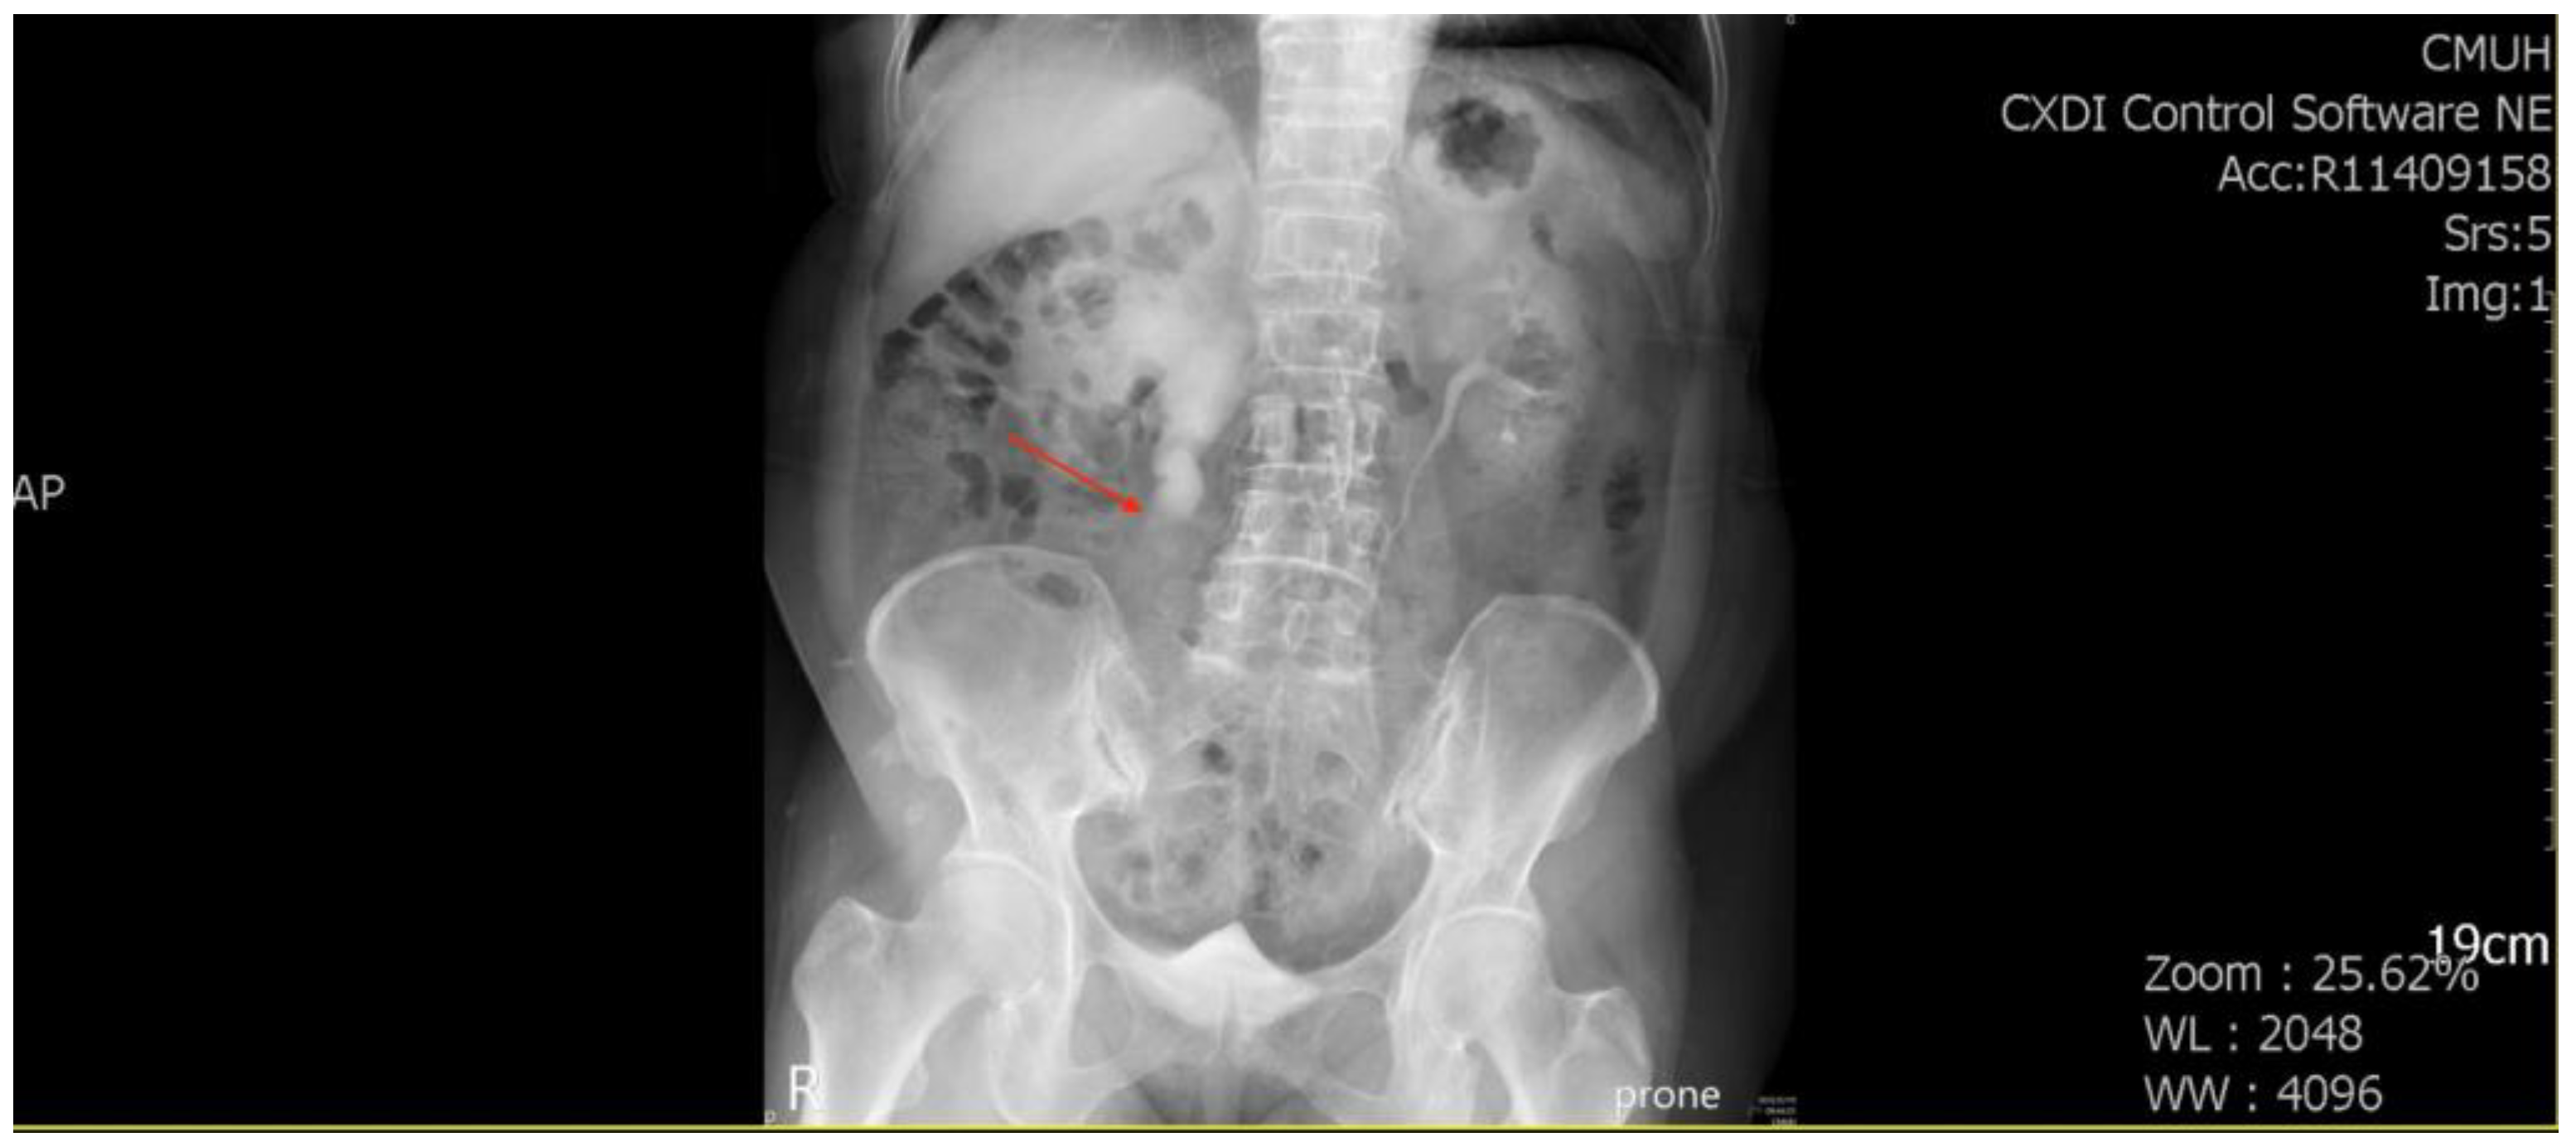

A 71-year-old female patient with a history of recurrent stone disease presented with abdominal pain. She denied a history of diabetes and hypertension. She had been treated for bilateral urolithiasis for 12 years, including a left kidney stone that had been treated with extracorporeal shock wave lithotripsy (ESWL), a right ureteral stone that had been treated with ureterorenoscopic surgery, and a right renal stone that had been treated with ESWL. She presented with symptoms of painless gross hematuria and abdominal pain in May 2022. The renal echo revealed right hydronephrosis and a small renal stone. Intravenous pyelography showed a small upper ureteral stone with obstruction at the right upper ureter (Figure 1).

Figure 1. Intravenous pyelography revealed an obstruction at the right upper ureter (arrowhead).